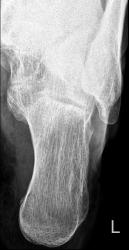

Гм...давайте так. Нарушения целостности костных струтур на предмет перелома я не вижу и по сию минуту, не смотря на активные убеждения в этом. То что показывают прицельно считаю это нормой- а именно медиальным отростком пяточного бугра. По поводу шопры то же не вижу, есть оссификация под пяточно-кубовидным суставом в боковой проекции. Больше ничего.

Согласен с коллегами Ольгой, Алексом и rentgengb1! Норма! Нечему отрываться по медиальной поверхности пяточной кости. Каким же должен быть механизм травмы, что бы оторвать малюсенький кусочек костной ткани от медиальной поверхности пяточной кости?

Добавлю свои 2 копейки, никаких указаний на дефект костной структуры не вижу. Даже если и представить что перез нами отрыв, то каков же механизм такой травмы? Особенно принимая во внимание крайне скудные ее (потенциально) проявления... Нет, я бы не сомневаясь сказал - норма.

Перелома не вижу, даже сомнений нет! написал бы норму.

Уважаемый rentgengb1 а ближе к медиальному отростку бугра пяточной кости вас ни что не смущает?

Нет не смущает, покажите пожалуйста прицельно, что Вас смущает.

Возраст пациента 46 лет.